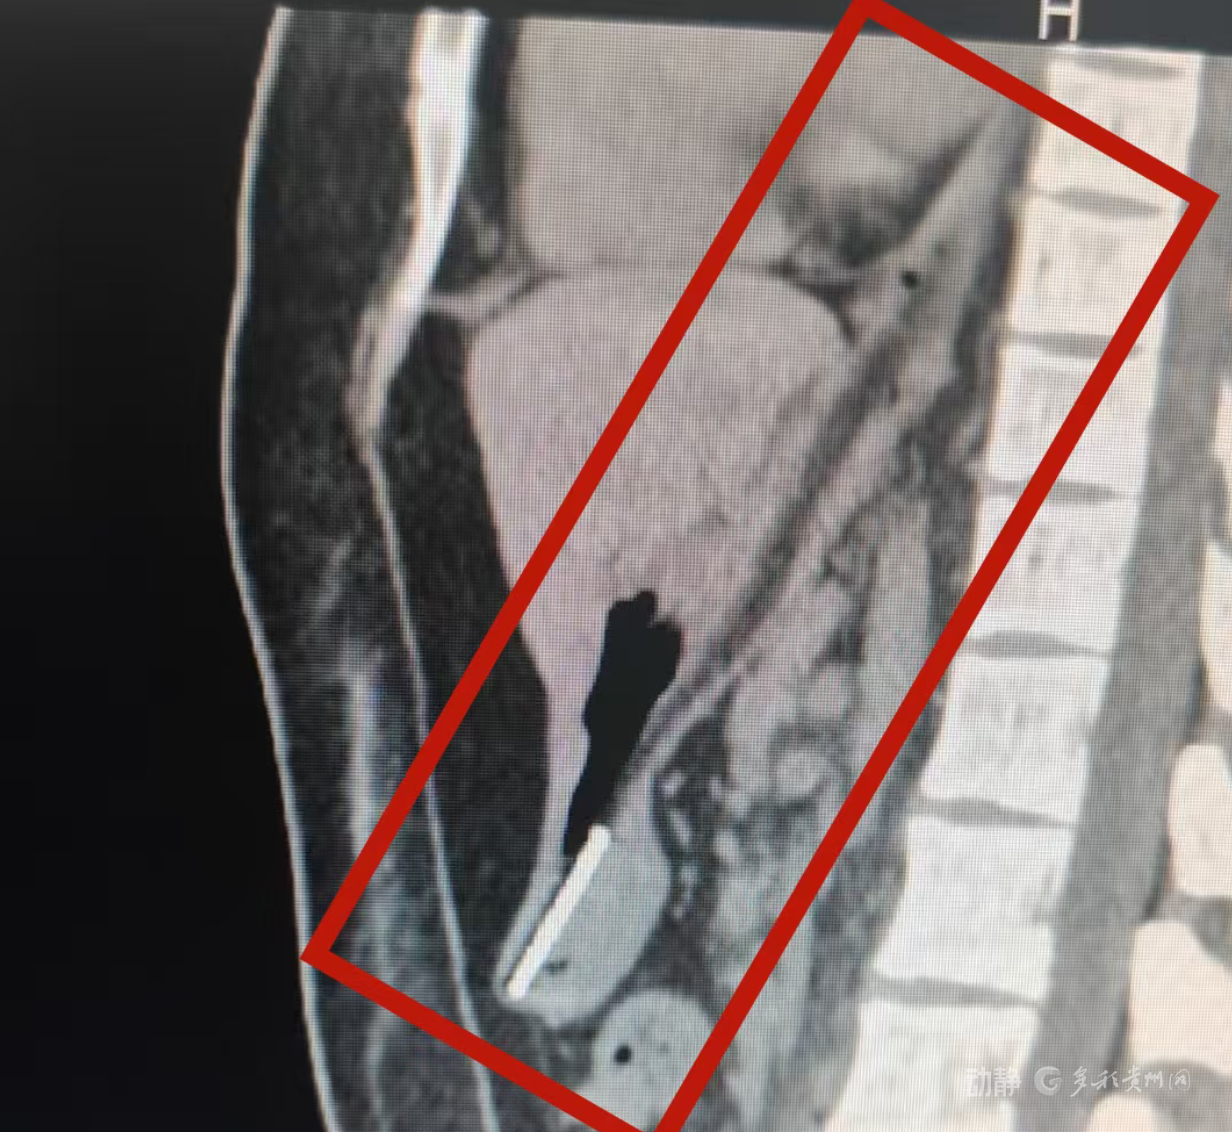

据悉,该患者因精神疾病发作不慎吞入整支塑料牙刷。接诊后,消化内科副主任医师蒋丽通过详细检查发现,牙刷卡在食管下段与胃入口(贲门)交界处,形成“两头受力”的危险状态:一端顶压胃壁,另一端斜刺食管壁。由于牙刷长度接近胃体充盈状态下的直径,若强行推进可能导致食管穿孔、纵隔感染或致命性大出血。

手术过程中,操作医生通过胃镜精准定位牙刷位置,使用圈套器套住牙刷中部后,需克服食管三处生理狭窄的挑战,将整支牙刷安全撤出。得益于医护团队的紧密配合,手术顺利完成,患者胃食管黏膜未出现明显损伤。